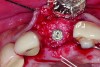

Placement of implant. Notice the bucco-palatal bone thickness gained from the ridge preservation technique.

Figure 2